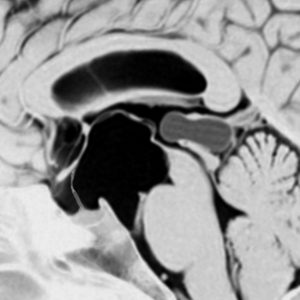

鞍上部クモ膜のう胞

20歳代の女性の無症候性のものです。水色に塗ったのがクモ膜のう胞です。特徴的なのは,下垂体柄が長〜く伸びて細くなっていることです,でも下垂体障害はでません。珍しいことですが,松果体のう胞(黄色の部分)が合併しています。治療の必要がないものです。